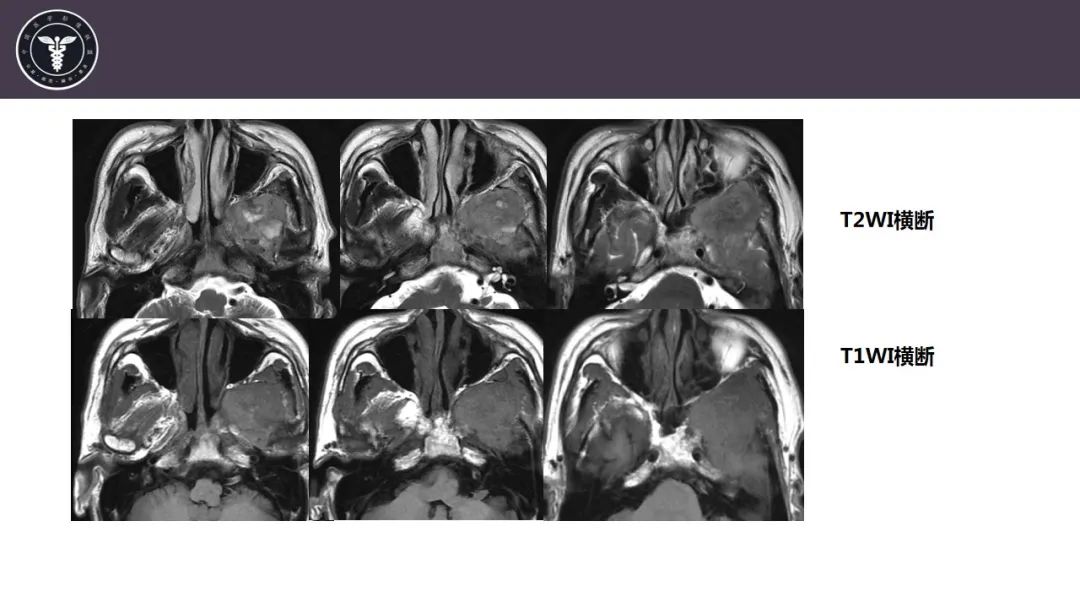

【病例】咬肌间隙肌纤维母细胞肉瘤1例MR诊断与鉴别-1

【病例】咬肌间隙肌纤维母细胞肉瘤1例MR诊断与鉴别-2